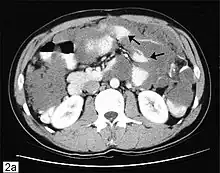

CT scanning is preferred to assess the extent of the tumor in the abdominopelvic cavity, though magnetic resonance imaging can also be used.[28] CT scanning can also be useful for finding omental caking or differentiating fluid from solid tumor in the abdomen, especially in low malignant potential tumors. However, it may not detect smaller tumors. Sometimes, a chest x-ray is used to detect metastases in the chest or pleural effusion. Another test for metastatic disease, though it is infrequently used, is a barium enema, which can show if the rectosigmoid colon is involved in the disease. Positron emission tomography, bone scans, and paracentesis are of limited use; in fact, paracentesis can cause metastases to form at the needle insertion site and may not provide useful results.[29] However, paracentesis can be used in cases where there is no pelvic mass and ascites is still present.[29] A physician suspecting ovarian cancer may also perform mammography or an endometrial biopsy (in the case of abnormal bleeding) to assess the possibility of breast malignancies and endometrial malignancy, respectively. Vaginal ultrasonography is often the first-line imaging study performed when an adnexal mass is found. Several characteristics of an adnexal mass indicate ovarian malignancy; they usually are solid, irregular, multilocular, and/or large; and they typically have papillary features, central vessels, and/or irregular internal septations.[31] However, SCST has no definitive characteristics on radiographic study.[33]